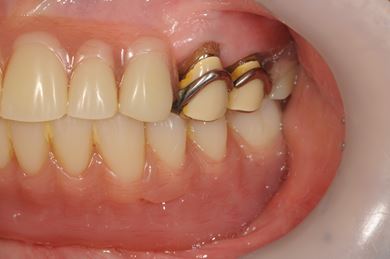

インプラント治療+オーバーデンチャー

| 性別/年齢 | 女性 / 85歳 | ||||||||||||||||||||||||||||||||

| 治療方針 | 下顎に2本インプラントを埋入し、アタッチメントをつけて、オーバーデンチャーを装着し、はずれにくく、安定した義歯を装着する。 | ||||||||||||||||||||||||||||||||

| 治療内容 | インプラント2本(テンポラリーインプラント)、アタッチメント、コバルトクロム床オーバーデンチャー | ||||||||||||||||||||||||||||||||

| 総治療費 | 1,540,350円 | ||||||||||||||||||||||||||||||||

| 治療期間 | 5ヶ月 |